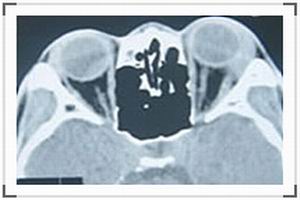

3.頭部放射線攝片顯示大塊(>15mm)的絮狀松果體鈣化或腦水腫徵象。